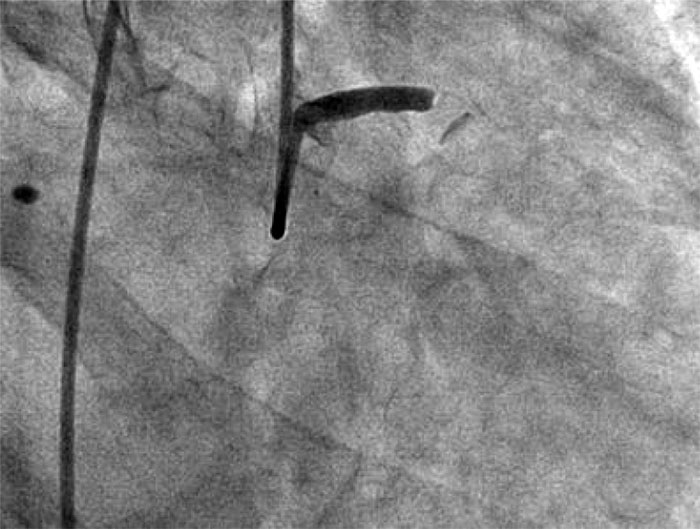

Urgent angiography showed occlusion of the LCA trunk without signs of antegrade contrast enhancement of the left coronary artery distal to the occlusion.

Fig. 1. LCA trunk occlusion